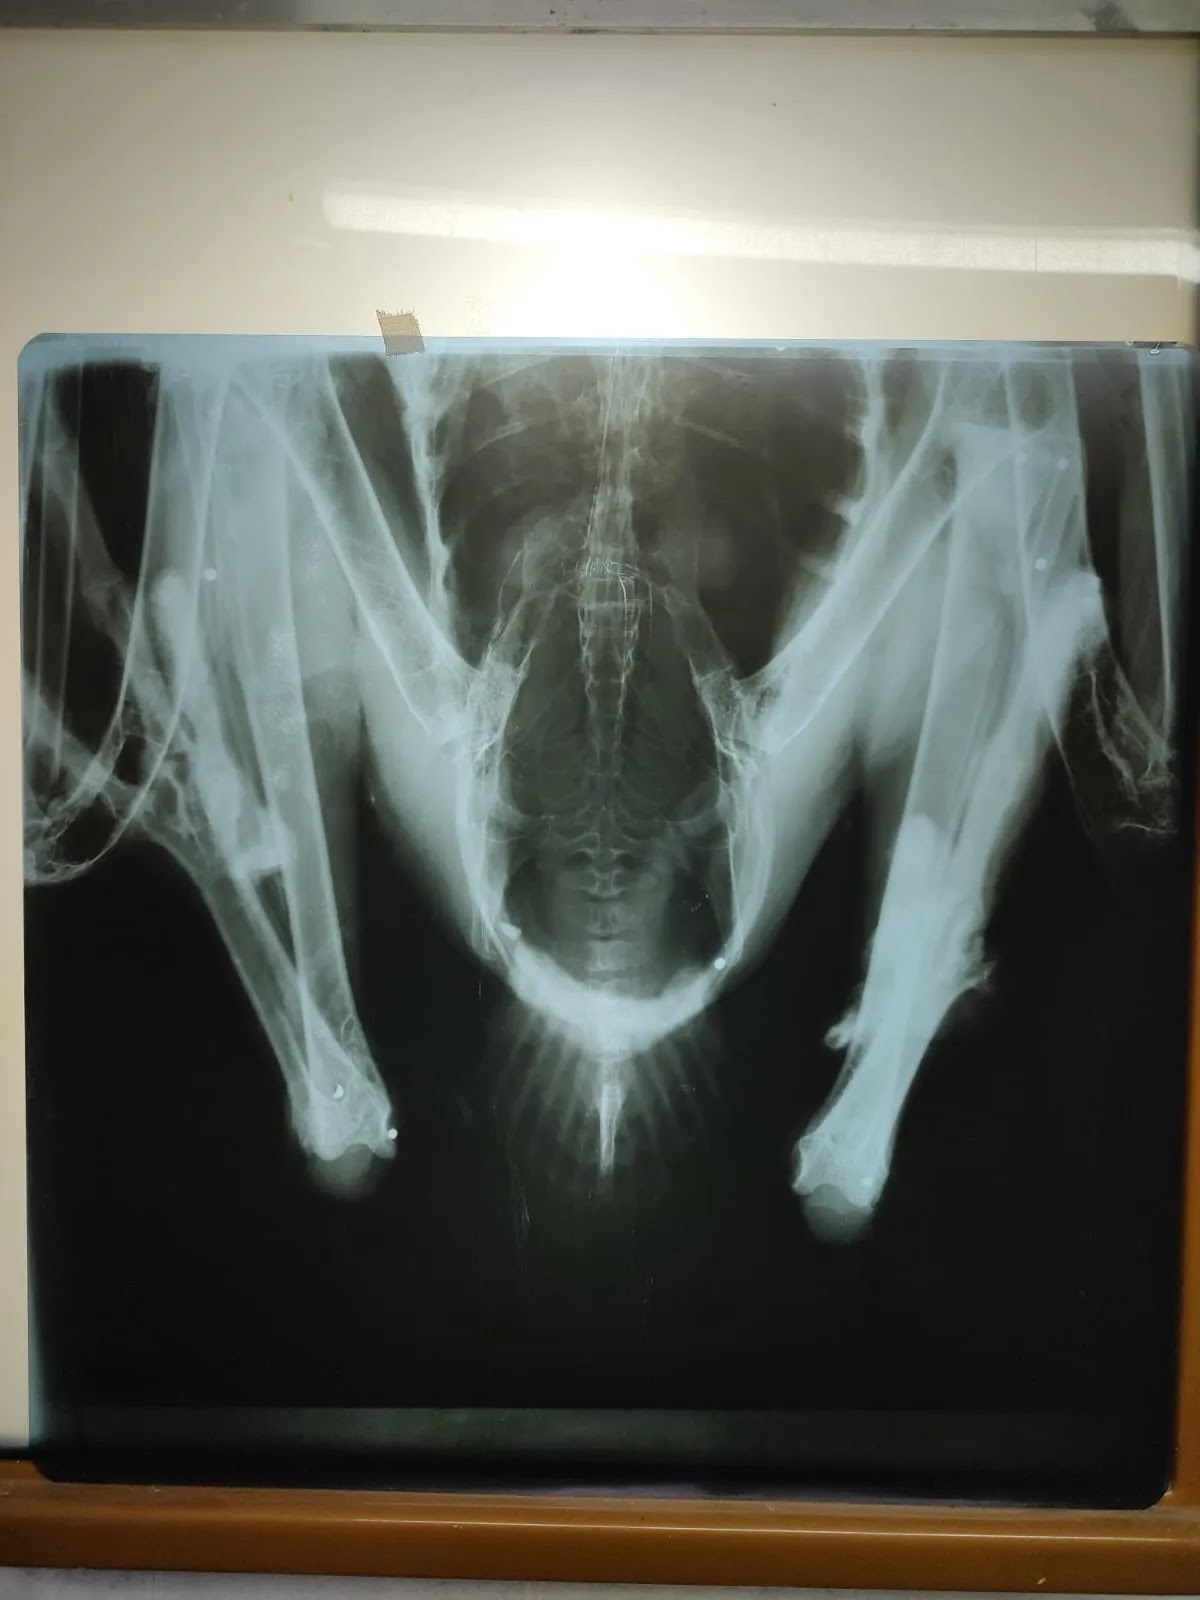

El análisis forense reveló un descubrimiento preocupante: el ave tenía 14 perdigones de plomo en su organismo, resultado de disparos con arma de fuego. Esta intoxicación prolongada por plomo no causó la muerte inmediata del cóndor, sino que resultó en un deterioro progresivo y agonizante.

Este incidente destaca nuevamente el grave impacto de la caza ilegal en especies protegidas por la ley. Los perdigones de plomo, comúnmente usados en cartuchos de calibre 12, pueden tener entre 24 y 36 gramos, una cantidad suficiente para envenenar al cóndor y provocar una muerte lenta.